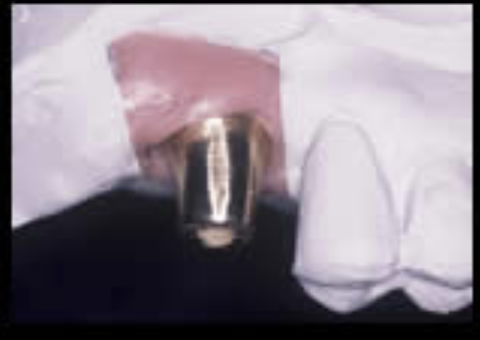

人工歯根と接合するアバットメントを示します。

治療過程

抜歯後、歯周病処置、歯内療法処置、咬合高径改善、プロビジュナルレストレーションを経て最終補綴をおこないました。